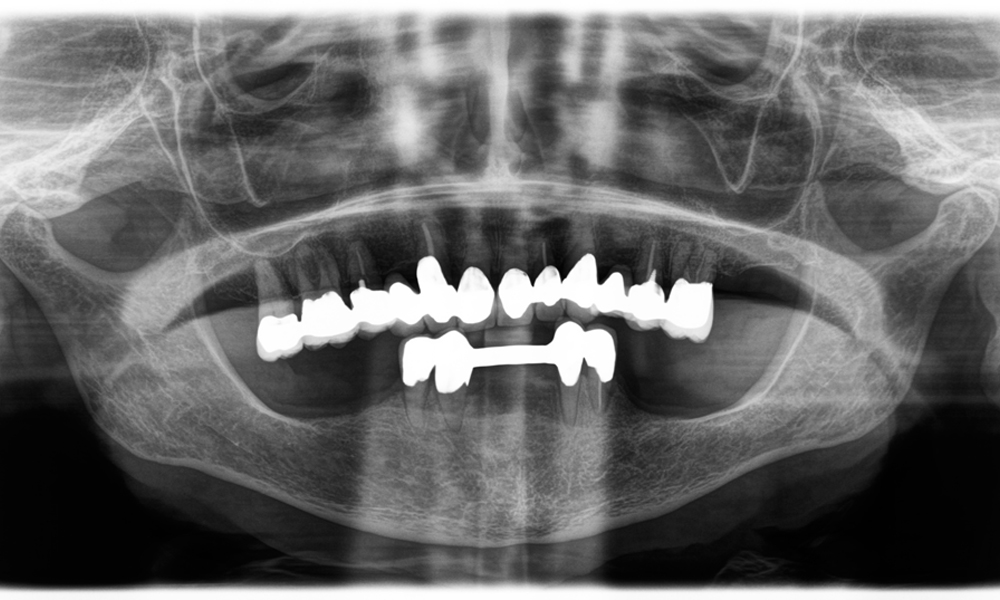

A x-ray, showing teeth and a zirconia crown, in front of a black background.

Figure 2: Replacement of a damaged zirconia crown: Precise removal and renewal of a damaged zirconia crown on tooth 6 with minimal material loss.